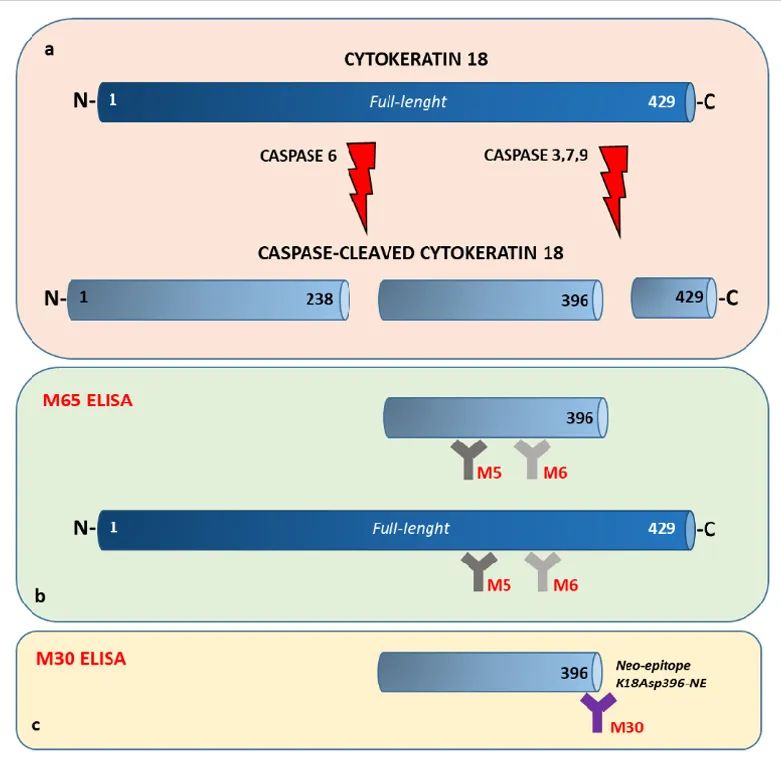

CK18是上皮细胞特异性表达的蛋白,有两种表达形式

半胱天冬酶(Caspase)裂解的CK18片段(CK18-M30)和 全长蛋白(CK18-M65)

CK18-M30

是CK18蛋白在上皮细胞凋亡过程中被半胱天冬酶(caspase)裂解产生的片段。在细胞凋亡的早期阶段,细胞内的一系列蛋白酶(如 caspase-3,-6,-7,-9)被激活。这些蛋白酶会特异性地识别 CK18 蛋白上的位点并进行切割,产生含新生抗原决定簇的M30片段。

CK18-M65

是从凋亡或坏死细胞中直接释放的未被裂解的完整CK18蛋白。在肝细胞坏死过程中,细胞会发生肿胀、破裂,细胞内容物包括 CK18 蛋白会非特异性地释放到血液中;同时在凋亡过程中,除了产生 M30片段外,也会有其他的 CK18 裂解产物,M65片段可以综合反映这些过程。所以,通过免疫测定法在人血清中检测M65,可以涵盖肝细胞坏死和凋亡两种情况,其在血液中的水平能够更好地体现总肝损伤的程度。

CK18 detection and distinction between M30 and M65 immunoassays.